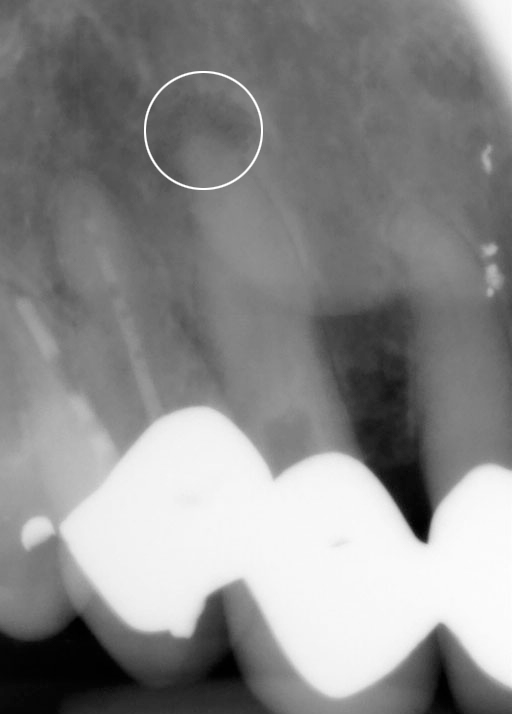

Op de eerste foto ziet uw een ontstoken kies in de rechter bovenkaak. We zien een grote kies met een ferme wortel. De punt van de wortel laat een zwarting zien. ( Zie de punt in de witte cirkel )